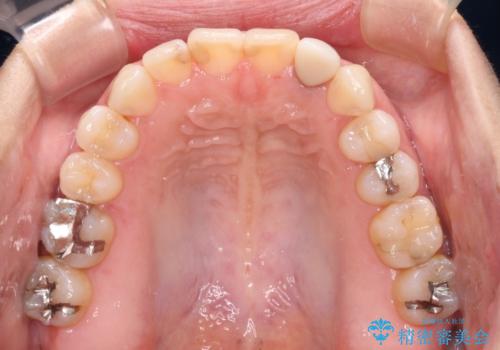

開咬と変色した前歯 インビザライン矯正とオールセラミッククラウン治療

- 前歯の開咬と失活により変色した前歯を気にして来院された患者様です。

開咬の治療は、前歯を閉じるように引っ張り出すよりも、上下臼歯を圧下(骨内にめり込ませる)させることで進める方が長期的に安定した歯列を維持できます。

インビザラインは臼歯の圧下を効果的に行えるため、インビザラインを用いて矯正治療を行うこととしました。

矯正治療が概ね終了した時点で前歯をオールセラミッククラウンにて補綴治療を行い、その後インビザラインにて細かい部分を仕上げていくことしました。